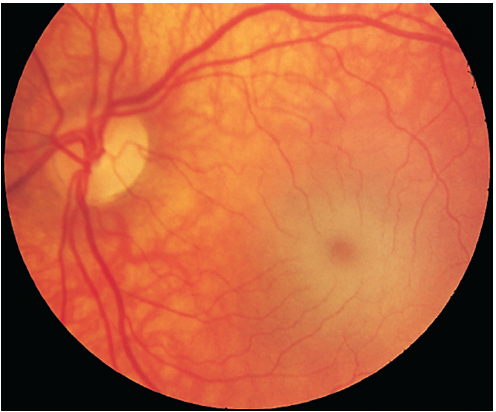

GM2 GANGLIOSIDOSIS - TAY-SACHS DISEASE

Metabolic disorder: Lysosomal lipid storage disorder

Genetics: HEXA gene

Inheritance: Autosomal Recessive

Most prevalent in Ashkenazi Jewish population

Clinical Features: Hyperacusis, no HSM.

Investigations: serum or leukocyte β-hexosaminidase A deficiency

Prognosis: few live beyond 3-4yo; death usually due to aspiration or pneumonia